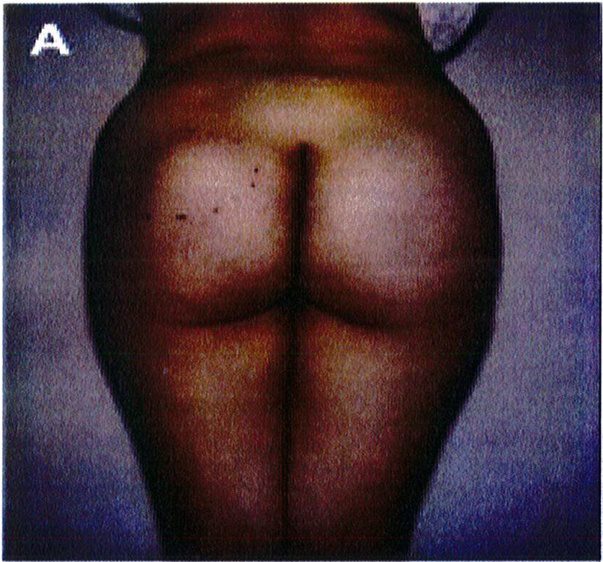

Để tránh tình trạng quá ngắn hoặc quá dài của vùng mông (hay còn gọi là mông dài/ngắn) thì tác giả đã kết hợp một phép đo đơn giản trước phẫu thuật, đo khoảng cách từ mào chậu phía sau tới đường ngang đi qua trung điểm nếp liên mông (khoảng cách A) và từ đường ngang đó tới nếp lằn mông (khoảng cách B) (Hình 1) đế tính vị trí chuẩn xác của khối im- plant.

Để tránh tình trạng phần mông trên được nâng lên quá mức, khoảng cách A thông thường phải gấp đôi khoảng B để có thể phù hợp cho nâng mông dưới cơ.

Nếu khoảng cách A ngắn hơn, nên sử dụng mặt phẳng trong cơ để tạo điều kiện cho khối im- plant được đẩy xuống thấp hơn 1 chút, giúp đạt được kết quả thẩm mỹ lý tưởng.

Hình. 1. Đánh giá trước phẫu thuật để lựa chọn bệnh nhân với mặt phẳng im- plant phù hợp.